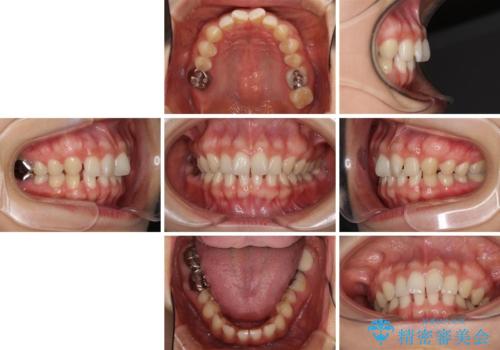

隙間だらけの歯列をきれいに インビザライン矯正とセラミック補綴治療

- 前歯の隙間と奥歯の目立つ銀歯を気にして来院された患者様です。

インビザラインにより下顎前歯の隙間を閉じるとともに、奥歯の咬み合わせを改善させることとしました。

矯正治療後には、銀歯のクラウンをセラミッククラウンへ替える補綴治療を行うこととしました。

左右奥歯の咬み合わせを変更させる必要があったため、治療期間は長くなることが予想されました。

1日22時間以上の装着時間をしっかりと守ってくださったので、順調に治療を進めることができました。